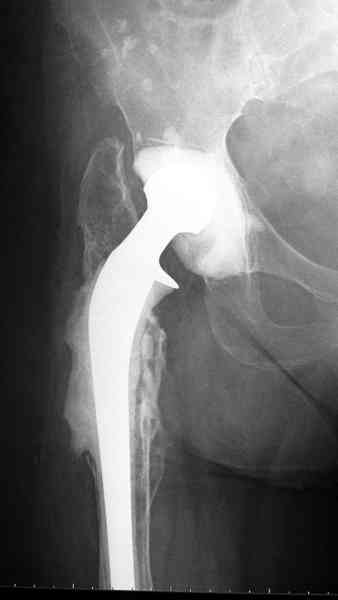

Приглашенный хирург установил ревизионный вариант бедренного компонента без замены ацетабулярного компонента, что осложнилось нагноением и свищами на уровне сустава и средней трети бедра. После двухгодичного безуспешного лечения перевязками и антибиотиками больная обратилась к нам на консультацию.

Повторная операция по удалению тотального протеза с irrigation&debridment, канал после очистки цемента обильно промыт и рассверлен римером.

Приготовлен цемент из расчета: Tobramycin 2.4 g (2 флакона), Vancomycin 2 млн (4 флакона) и 2 упаковки цемента с добавлением дополнительного флакона цементной жидкости.

После обработки ацетабулярного компонента, ещё в мягком цементе в полости вертлужной впадины головкой бедренного компонента сделана выемка для головки, чтобы свежий цемент не прилипал к головке. Головку бедренного компонента завернул обычной стерильной фольгой, которую после образования выемки отлепил от головки.

Для спейсера в бедро использовал старый длинный бедренний компонент меньшего диаметра, облепленный со всех сторон цементом с антибиотиком.